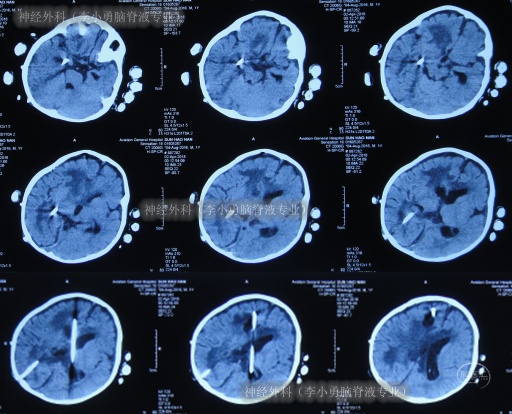

2018年2月9日(第3家医院治疗10天),接受了经右枕侧脑室腹壁外引流术(有分流泵),术后当天查头部CT示引流术后状态(图-5)。

图-5:2018年2月9日头部CT

2018年2月12日(右侧脑室腹壁外引流术后3天),引流的脑脊液细菌培养未检出细菌,但间断发热,继续抗感染治疗期间加用人免疫球蛋白,头部核磁增强示脓肿未减轻,脑室仍扩张(图-6)。

图-6:2018年2月12日头部核磁增强